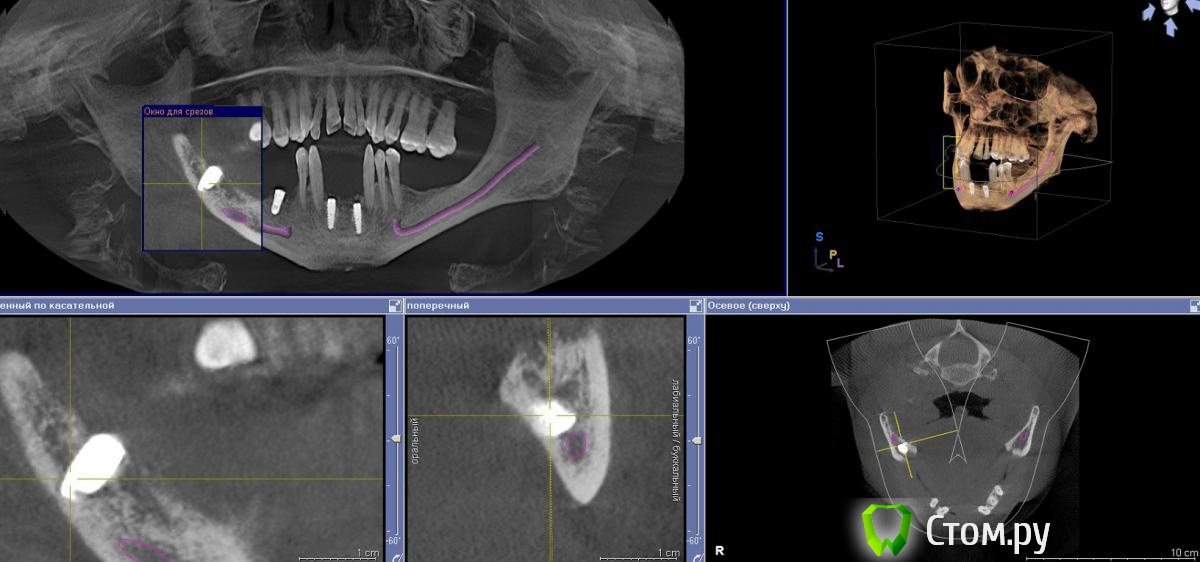

samanta66 Опубликовано 12 октября, 2014 Поделиться Опубликовано 12 октября, 2014 Уважаемые доктора, нужна консультационная помощь.3 месяца назад поставлены импланты на месте 32 и 42, 36 и 38 зубов (если не ошибаюсь с нумерацией), скоро протезирование. Сохраняется чувство легкого онемения части подбородка. Периодически (особенно при и сразу после жевания) чувствую стискивание зубов (33 и 34), онемение или "мурашки", покалывание в правой части губы. Затем указанные симптомы проходят, но периодически (несколько раз в день) появляются снова. По ощущениям их интенсивность всё-таки уменьшилась со временем.1. Каковы перспективы? Можно ли надеяться на полное восстановление чувствительности. Не будет ли проблем при протезировании (установлении абатмента и коронок)?2. Оцените качество установления имплантов? ОПТГ приложила. Спасибо. Ссылка на комментарий

SergioS Опубликовано 12 октября, 2014 Поделиться Опубликовано 12 октября, 2014 (изменено) Интенсивный выбор позиции имплантов справа. Сходите на консультацию к другому доктору и сделайте кт. Чем раньше тем лучше. Изменено 12 октября, 2014 пользователем SergioS Ссылка на комментарий

faity Опубликовано 12 октября, 2014 Поделиться Опубликовано 12 октября, 2014 компрессия НЧК имплантом возможна, +1 к КТ. чем раньше тем лучше Ссылка на комментарий

samanta66 Опубликовано 13 октября, 2014 Автор Поделиться Опубликовано 13 октября, 2014 КТ сделала, прилагаю.Пожалуйста, прокомментируйте. Ссылка на комментарий

faity Опубликовано 13 октября, 2014 Поделиться Опубликовано 13 октября, 2014 впритирку имплант стоит, я бы выкрутил Ссылка на комментарий